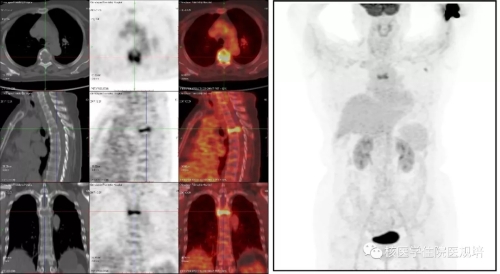

18F-NaF PET/CT乳腺癌骨转移-PET···